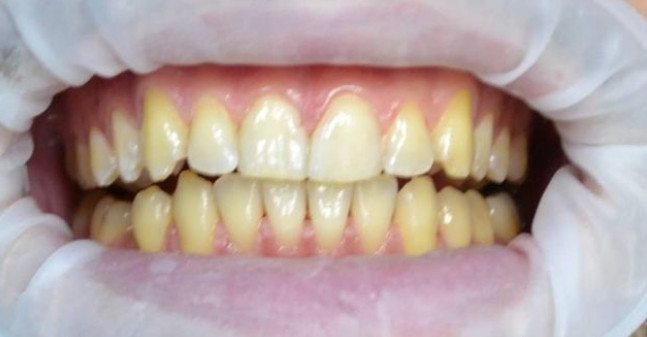

Центр стоматологии НЕБОЛЬСИН

Профгигиена

Жемчужная чистка зубов

Доктор: Евченко Надежда Владимировна